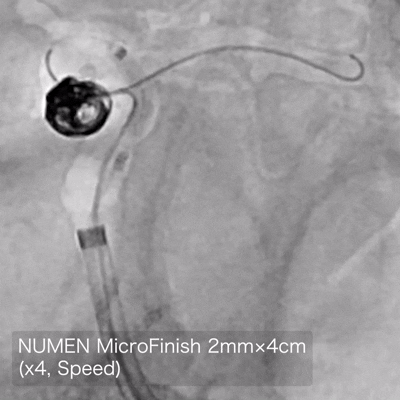

NUMEN Case 17